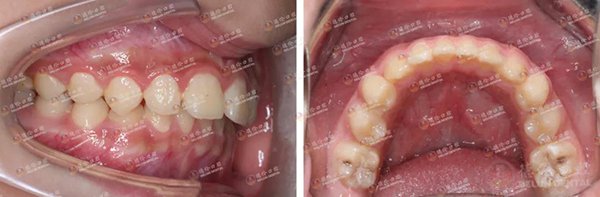

故事二中的主人公是三姐弟,大姐矫牙后认为李医生无论是医术还是医德都很nice,遂推荐弟弟妹妹也来矫牙。李医生说,弟弟主要的问题是下颌后缩,侧面观似“鸟嘴”样,前牙呈深覆盖,此番矫正的目的是将他的下颌往前导,改善他的面形。妹妹则是牙齿排列不齐所引起的咬合紊乱。

弟弟矫正前(左)与矫正后(右)对比照

妹妹采用的是发展比较早,技术比较成熟的传统金属自锁矫治器